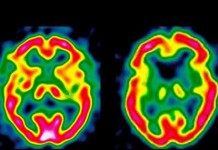

Старческого маразма больше нет: изобретена вакцина против болезни Альцгеймера

Группа канадских ученых и фармацевтическая компания GlaxoSmithKline нашли способ стимуляции естественных защитных механизмов головного мозга у пациентов с болезнью Альцгеймера. Болезнь Альцгеймера характеризуется образованием в...

Травма головы увеличивает риск развития болезни Паркинсона

Американские ученые установили, что у людей, перенесших травму головы и подвергающихся воздействию пестицидов, болезнь Паркинсона развивается в три раза чаще. Травма головы и воздействие...